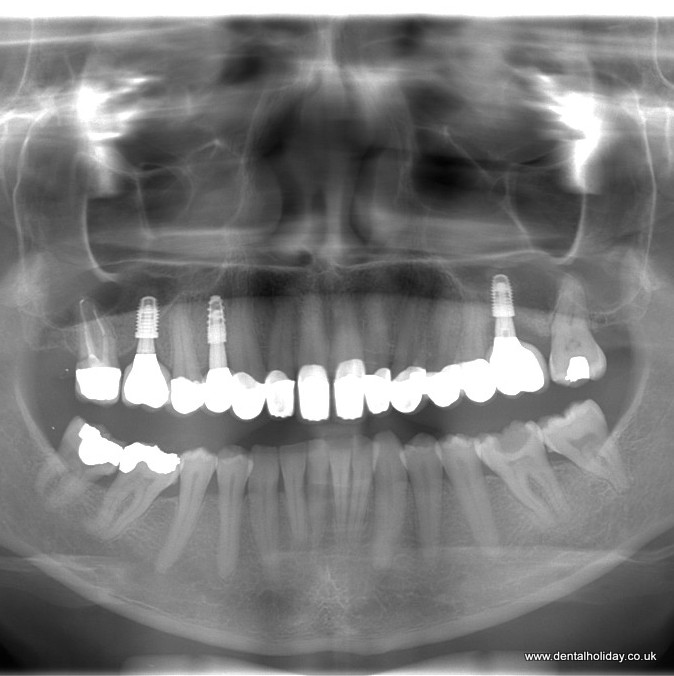

This process took 3 visits, each with an overnight stay, and as you can see from the x-ray, it was 3 dental implants supporting 13 crowns. Each time she stayed in a local hotel that overlooks the river and is close to the famous Piešťany spa island.